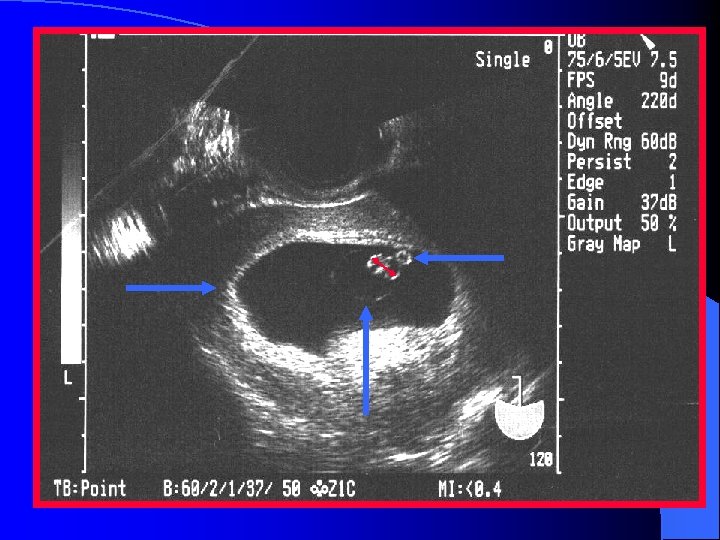

Definite Ectopic Pregnancy A thick, brightly echogenic, ring-like structure located outside the uterus with a gestational sac containing an obvious fetal pole, yolk sac or both.

Interstitial Ectopic Pregnancy l Implantation near the insertion of the fallopian tubes l Highly vascular area l Suspect when GS is not centrally located l Demonstration of endometrial mantle is critical to the diagnosis